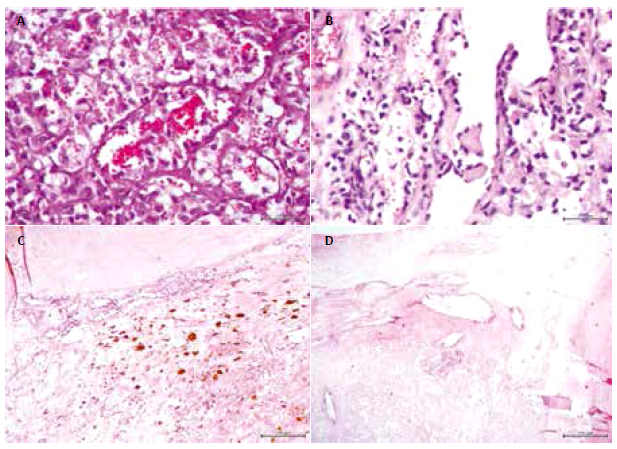

Se reevaluó el caso el año 2014, decidiendo reintervenir quirúrgicamente. En la segunda cirugía se apreció macroscópicamente una masa blanquecina que infiltraba retroperitoneo de consistencia calcificada, ubicada en el polo inferior del bazo, el cual se encontraba macroscopicamente hipotrófico en su parte superior. Se resecó la masa tumoral en bloque y se envió a patología, quienes describieron un bazo de 1800 mg de 22x17x12cm, color grisáceo, con zonas mixoides, hemorrágicas y necróticas, y 30% de áreas calcificadas (Figura 1), de aspecto multinodular con trayectos bien definidos que afectaban casi todo el espécimen. Al examen microscópico se apreciaron canales vasculares con células endoteliales altas y otras de aspecto histiocitario (Figura 2a), con proyecciones papilares (Figura 2b). Las células mostraron hemofagocitosis, hemosiderina luminal (Figura 2c), cristales de colesterol con reacción xantomatosa y calcificación distrófica (Figura 2d). El examen inmunohistoquímico reveló que las células fueron positivas para la línea endotelial CD31, Factor VIII, marcadores histiocíticos CD68, y ki67 negativo (Figura 3). Por todo lo anterior se catalogó al tumor como un angioma de células litorales esplénico. El paciente luego de la cirugía inició controles periódicos sin evidenciar recidiva local o a distancia, hasta la fecha del presente reporte.

Con respecto a los estudios inmunohistoquímicos, la mayoría de casos reportados expresó el marcador CD68, Factor VIII, CD8 y CD34; mientras que, una menor cantidad expresó lisozima y CD31. Peckova et al. revisó 25 casos de ACL y encontró que los marcadores que tuvieron mayor intensidad exclusivamente para las células litorales en el ACL fueron Claudin-5 y VEGFR-2, mientras que WT-1 se expresó fuertemente en el citoplasma de células esplénicas que no tenían ninguna alteración 4. La evaluación inmunohistoquímica en nuestro caso resultó positiva para CD31, Factor VIII, CD68; y fue negativa para Ki67, demostrando así su estirpe de neoplasia benigna con un bajo porcentaje de crecimiento. El marcador Factor VIII y CD31 demuestra la diferenciación endotelial mientras que el marcador CD68, lisozima y CD 21 demostraron la diferenciación histiocítica. Para el diagnóstico de ACL es fundamental demostrar ambas diferenciaciones y nuestro paciente las presentó.